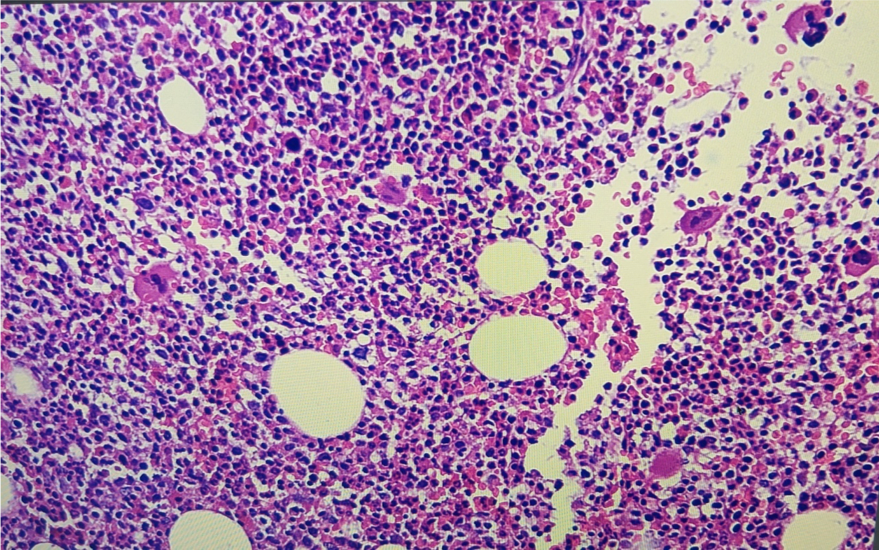

Repeat USG done at YMC-normal Bone marrow was done as had bicytopenia – to rule out the involvement of marrow by the disease process. Previously done duodenal biopsy slide was brought and subjected to 2nd opinion.Fig2

Hospital course: The Patient was admitted to the high dependency unit.Correction of dyselectrolemia. IV fluids . Empirical antibiotics. Supplementation vitamin B12, folate, B complex. Blood products – platelet transfused once and one unit of pack cells. Bone marrow was done in view of severe bicytopenia.

Upon treatment patient’s condition improved, the dyselectrolemia was corrected.bonemarrow showed features of peripheral destruction and hemophagocytosis.secondary hemophagocytosis secondary to GI pathology was considered.